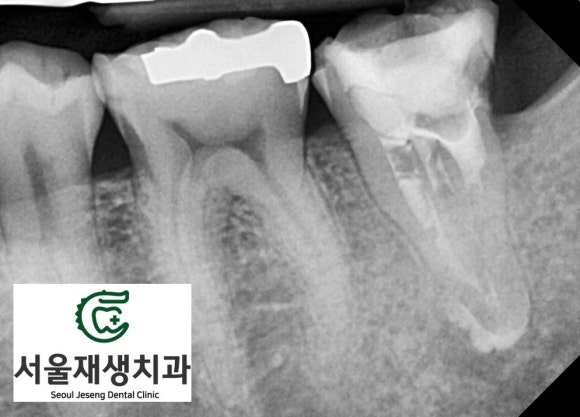

뿌리끝까지 꼼꼼하게 약제를 채워넣고,

치아의 머리도 레진이라는 재료로 충전하여 보강해줍니다.

이제 헬멧(=크라운)을 씌워 머리를 보호해주면 치료는 종료됩니다.